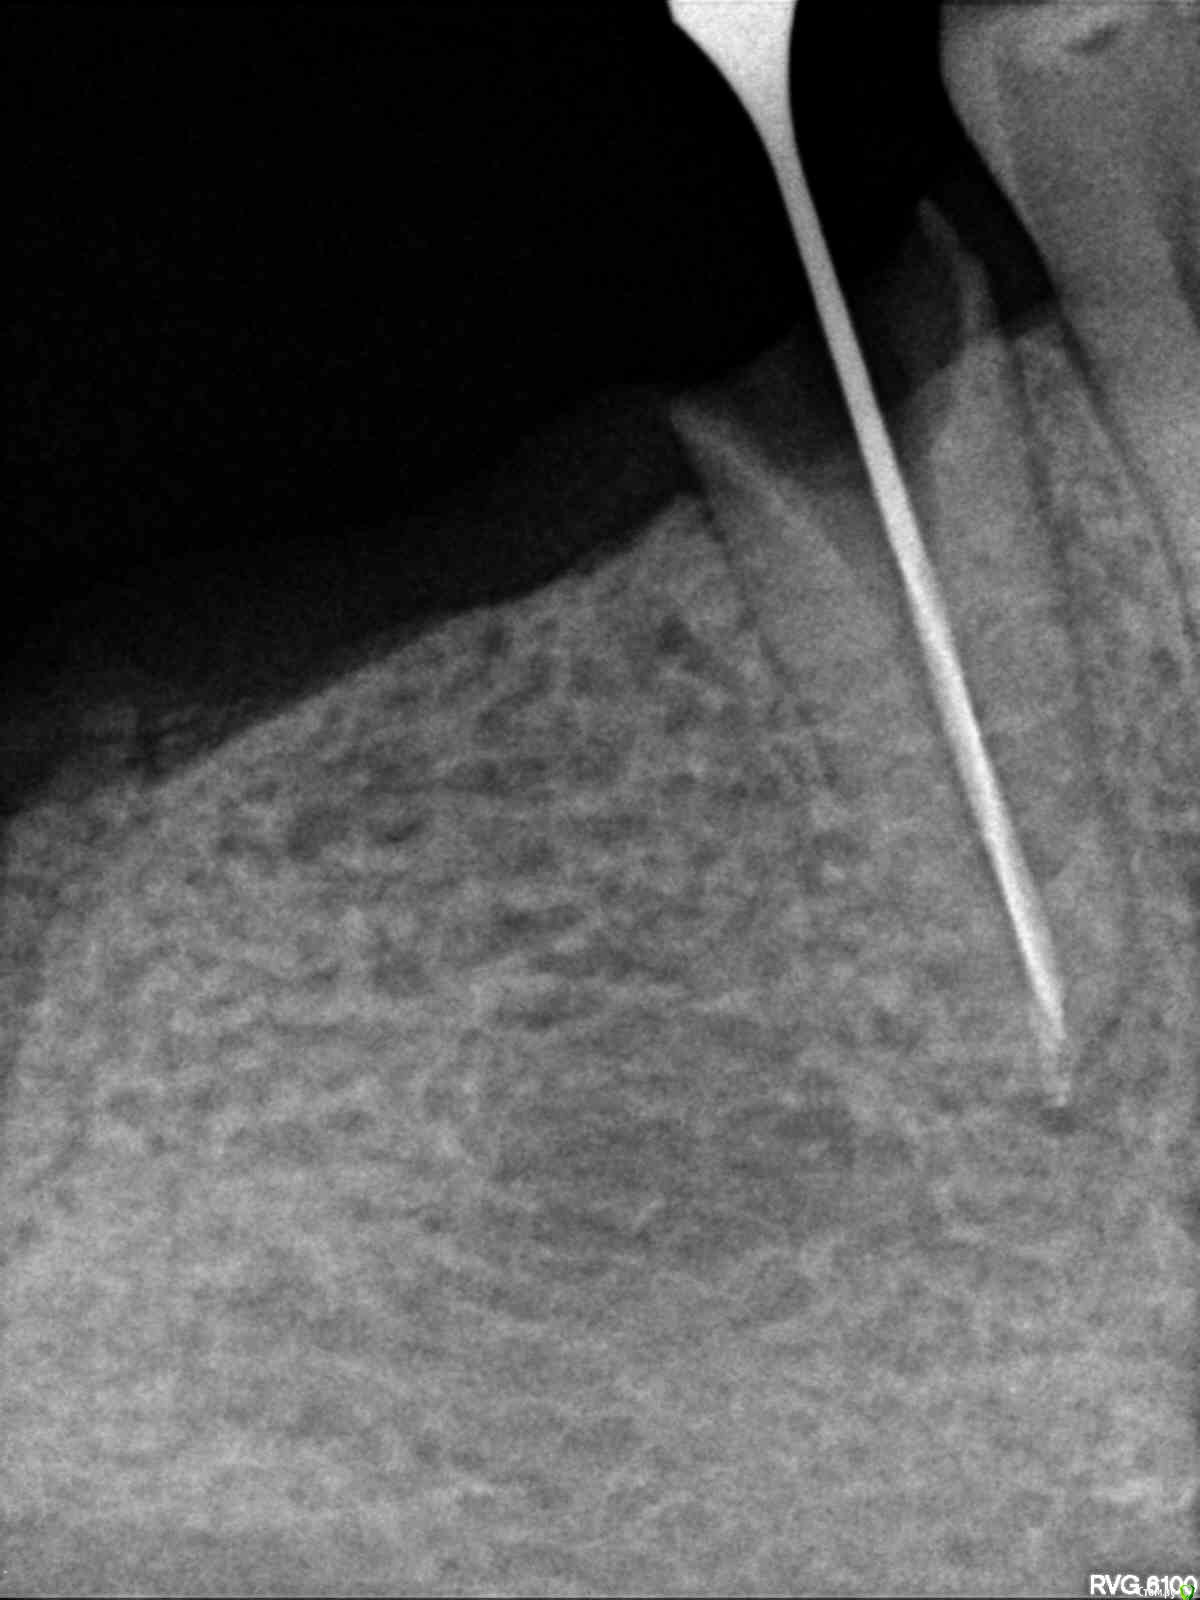

Некий Опубликовано 27 апреля, 2017 Поделиться Опубликовано 27 апреля, 2017 Добрый день!Ранее ношенные "мосты" прохудились и ушли в утиль.Сейчас стоит вопрос принятия "правильного" решения.ОПТГ был сделан еще в ноябре 16г.С тех пор произошли изменения:47 - удален. Заживал очень долго. Несколько раз удалялись секвестры.45 - делается под вкладку. Снимок прилагаю.37 - был сильно разрушен. Восстановлен ниже уровня десны на 3 штифтах. Снимок до восстановления.Доктор предлагает 2 "моста": 34-37 и 45-48. Напрягает состояние 37 и 45 зубов.1. Не получу ли в самое ближайшее время после установки мостов проблемы?2. Не сильно ли углублен канал под вкладку у 45го? Затемнение под корнем - это ни какая-либо проблема?3. Какие еще варианты могут быть при данной ситуации? Большое спасибо за Вашу помощь! Ссылка на комментарий